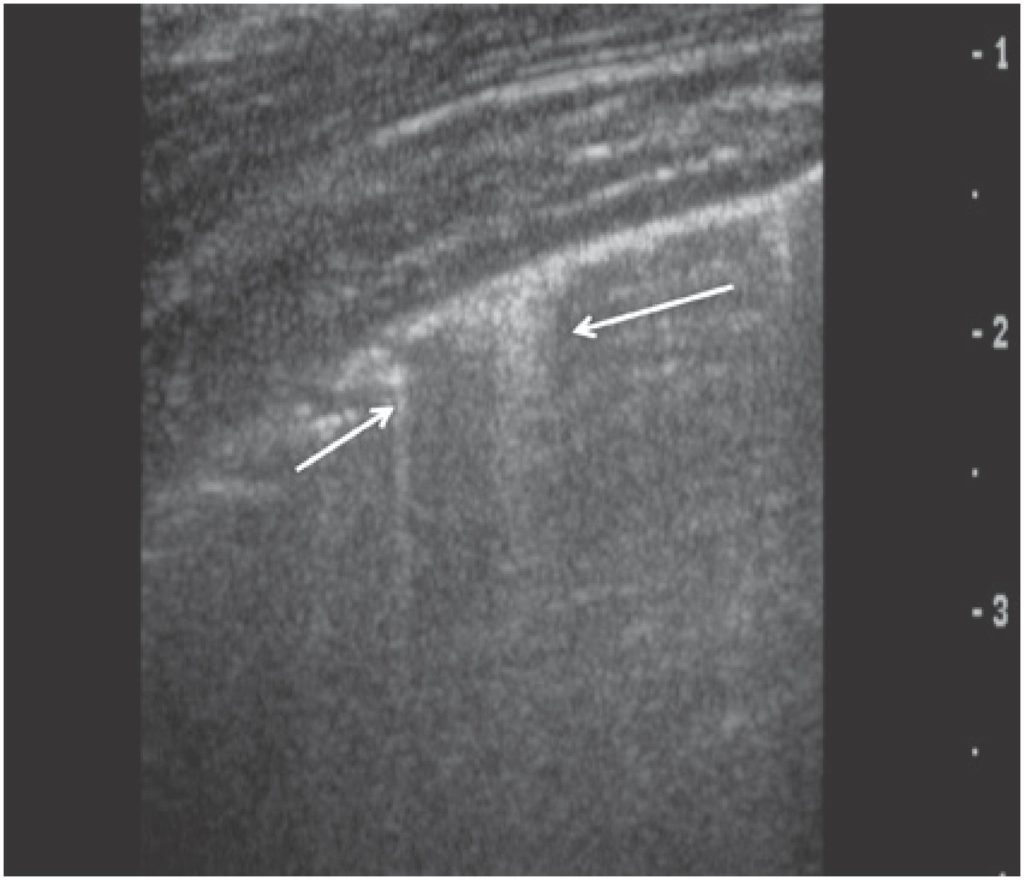

O exame ultrassonográfico do tórax avançou nas últimas décadas, sendo utilizado para o diagnóstico de inúmeras condições patológicas, e fornecendo informações qualitativas e quantitativas. Os pulmões aerados e o arcabouço ósseo do tórax representam barreira sonora para o estudo ultrassonográfico, gerando artefatos que, bem conhecidos, são utilizados como ferramentas diagnósticas. Eco pleural normal, linhas A, linhas B, linhas C, linhas E e Z (conhecidas como falsas linhas B) são artefatos com características peculiares. Os padrões de consolidação e de pneumotórax também são bem estabelecidos. Alguns protocolos têm sido utilizados no manuseio dos pacientes: Blue Protocol, Protocolo FALLS e Protocolo C.A.U.S.E são exemplos de três propostas que, por meio da associação entre os artefatos, permitem sugerir diagnósticos precisos. A ultrassonografia de tórax, aliada à radiografia de tórax, muitas vezes é suficiente para o diagnóstico e a conduta das afecções pulmonares e da parede torácica. Trata-se de ferramenta diagnóstica de grande valia para médicos radiologistas, emergencistas e intensivistas.